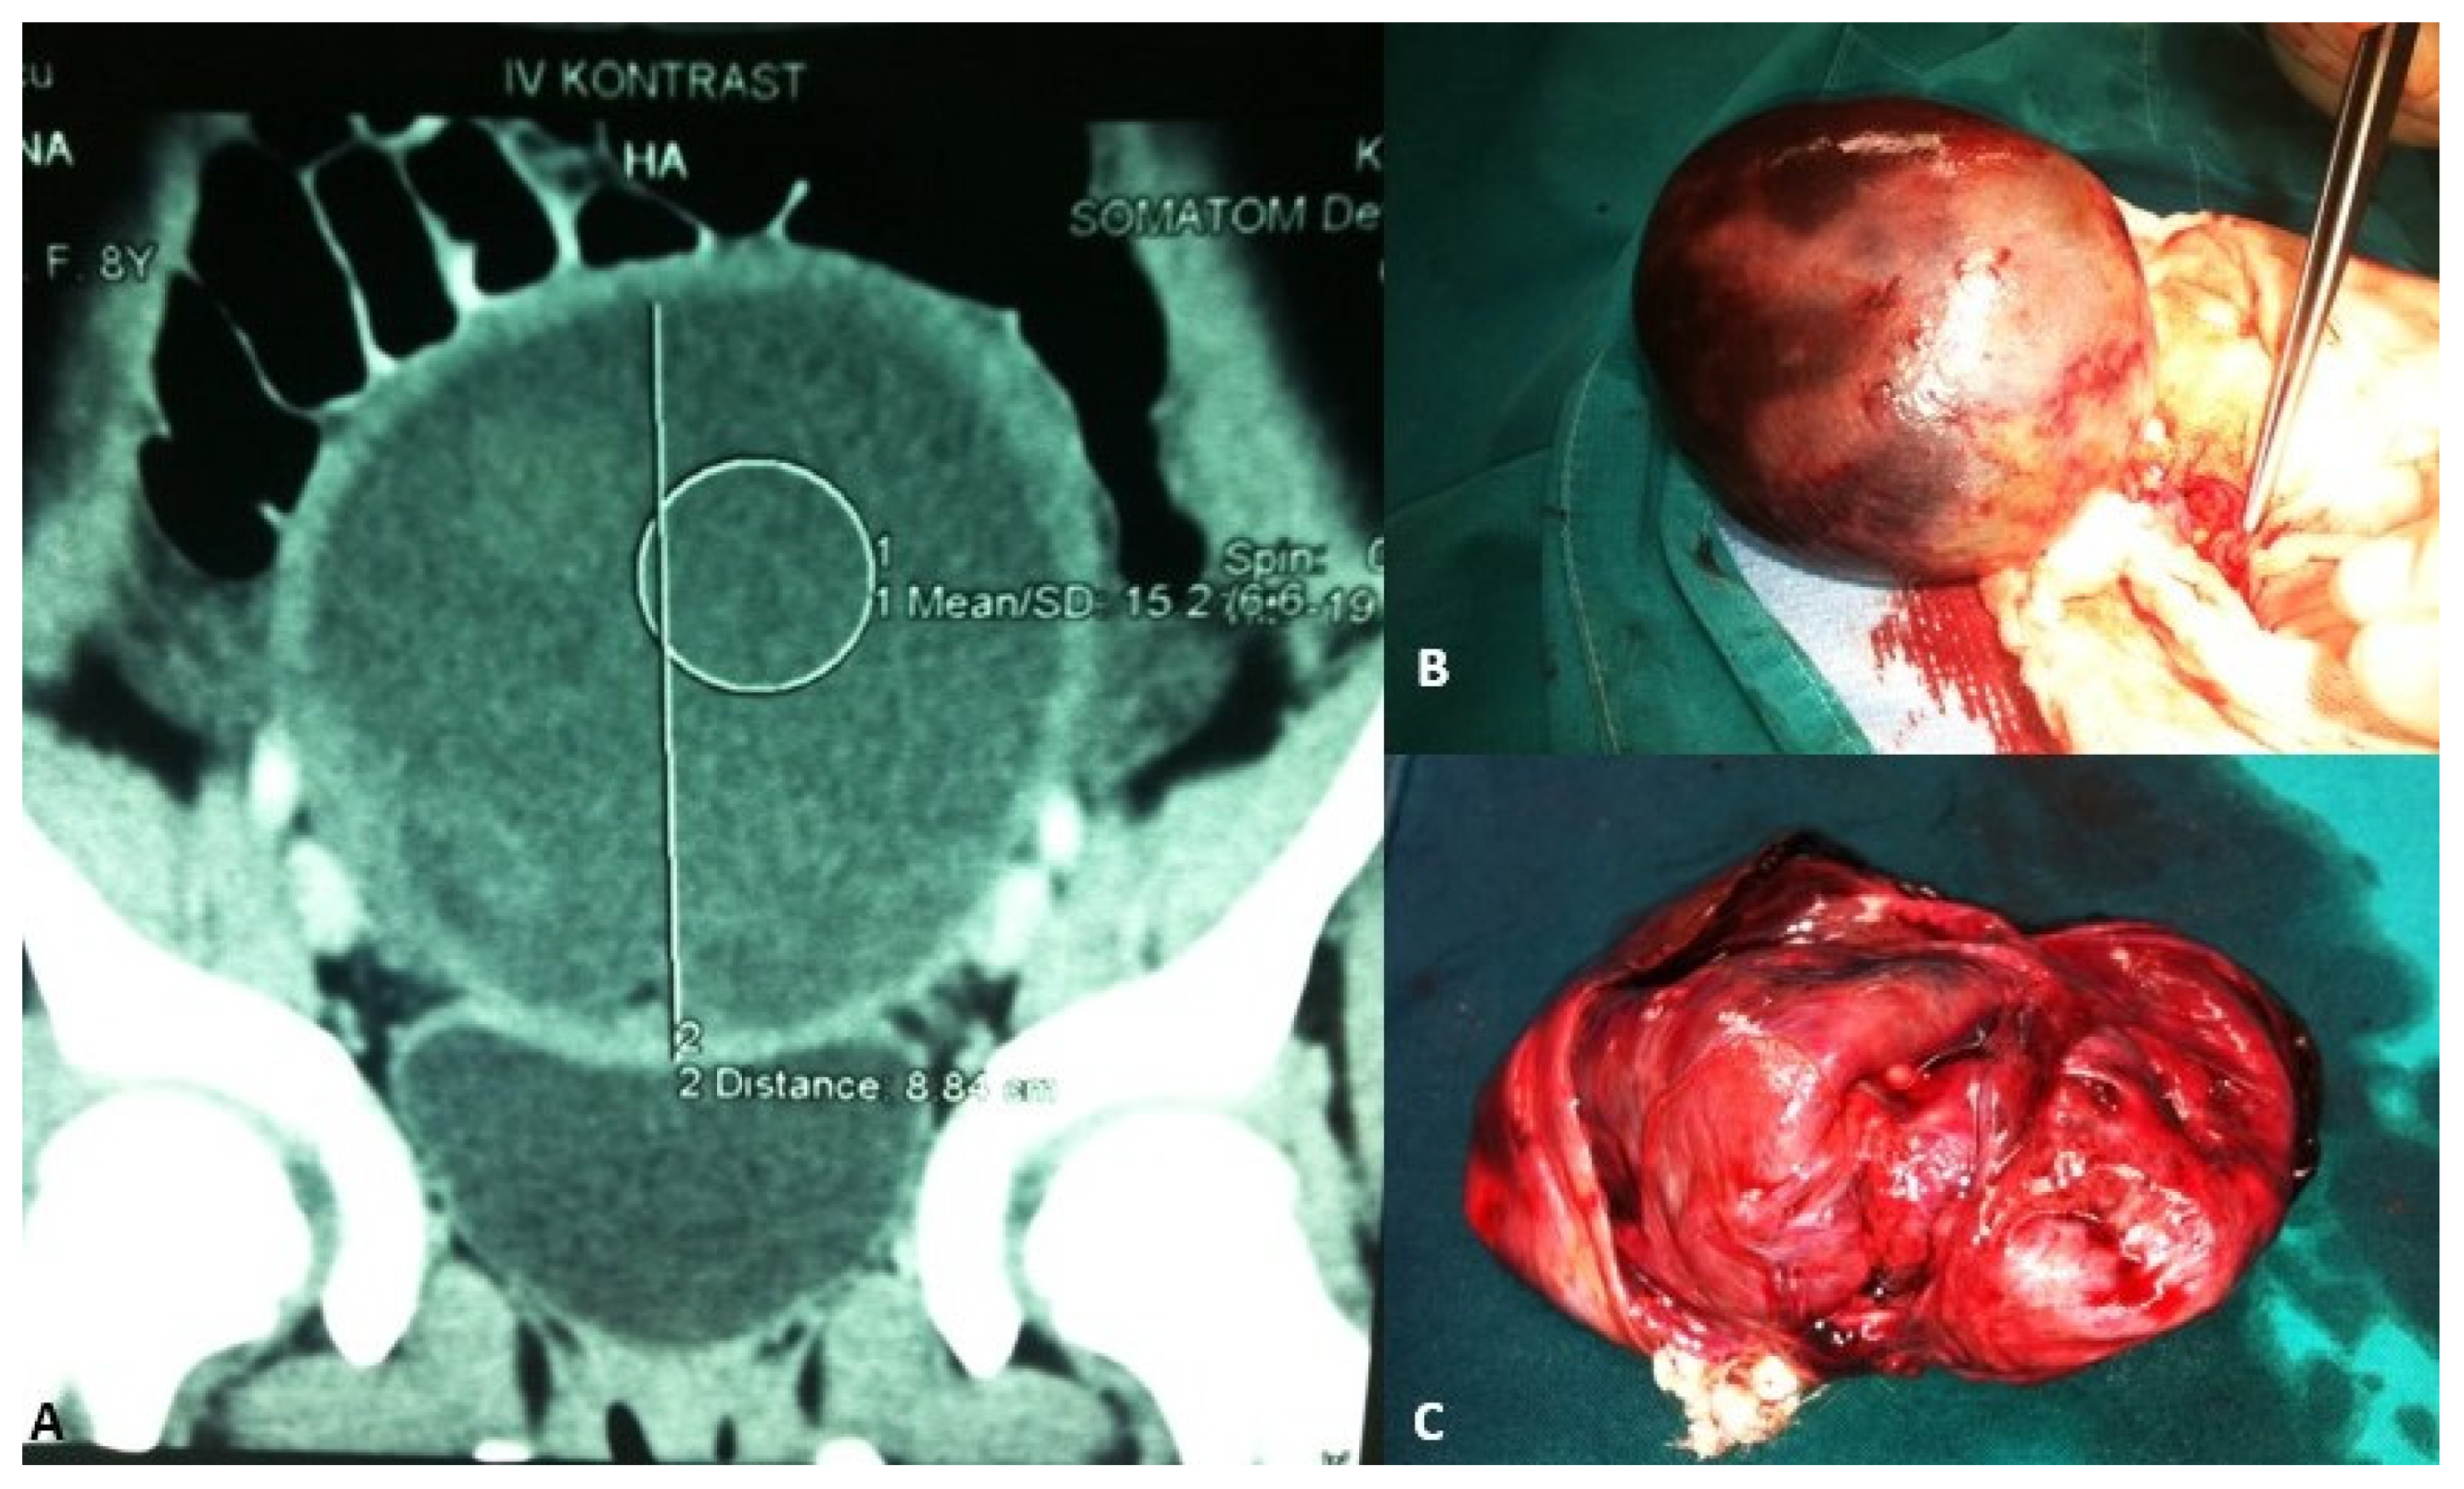

Figure 2.

A 13-year-old adolescent presented to the emergency room because of recurrent crampy abdominal pain that lasted a short time and then subsided. She had had the symptoms for about a week. An abdominal ultrasound was performed, which showed a mass in the pelvis. (A) MSCT of the abdomen revealed a 9.1 × 8.8 cm solid cystic mass in the right ovary that was not perfused; (B) Intraoperatively, a torquing, partially necrotic tumor of the ovary was noted; (C) Pathohistological findings were consistent with a mature teratoma of the right ovary. Source: Archive of the Department of Pediatric Surgery, University Hospital of Split.